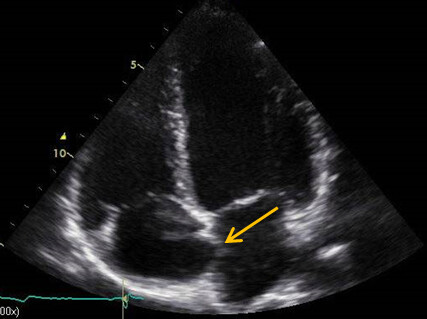

Um die Frage nach einem wirksamen Shunt zu präzisieren, erfolgte eine Rechtsherz-Echokardiografie mit Kontrastmittel (KM). Hierbei konnte sowohl in Ruhe als auch unter Valsalva ein Übertritt von Bubbles auf Vorhofebene dokumentiert werden (Abb. 1C / D). Unter Berücksichtigung der zurückhaltenden Einstellung der Patientin und der fehlenden neurologischen Residuen, die für keine gesicherte paradoxe Embolie sprachen, wurde eine Medikation mit ASS eingeleitet und die Patientin neurologisch wiederholt untersucht. Sie blieb bisher beschwerdefrei.

Abb. 3: Rechtsherz Echokardiografie, Credits: Perings